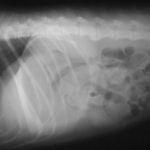

術前レントゲン

腹部臓器が胸腔内に脱出し、腹部と胸部の境界および心臓や肺の陰影が不明瞭になっています。また、胸腔内に消化管のガス陰影が認められます。

術後レントゲン

腹部臓器が腹腔内に戻り、腹部と胸部の境界および心臓や肺の陰影が明瞭に見えるようになりました。